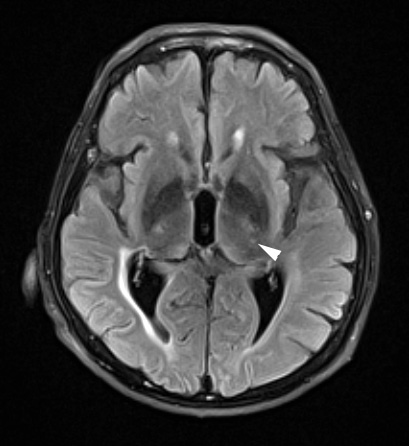

The dorsal part of the thalamus shows slight patchy hyperintensity in this FLAIR scan.